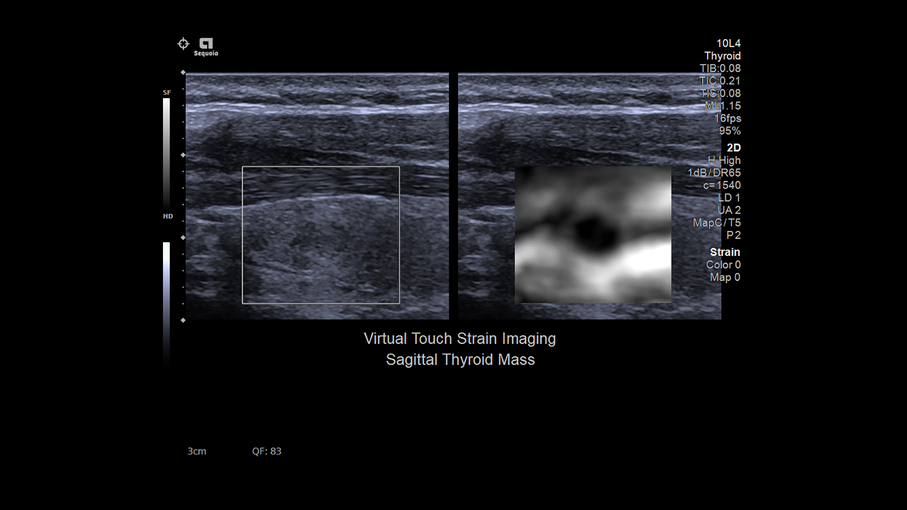

Кроме новой техники, можно заказать восстановленные медицинские системы: ультразвуковые сканеры, томографы, флюороскопы, ангиографы и хирургические установки С-дуга.